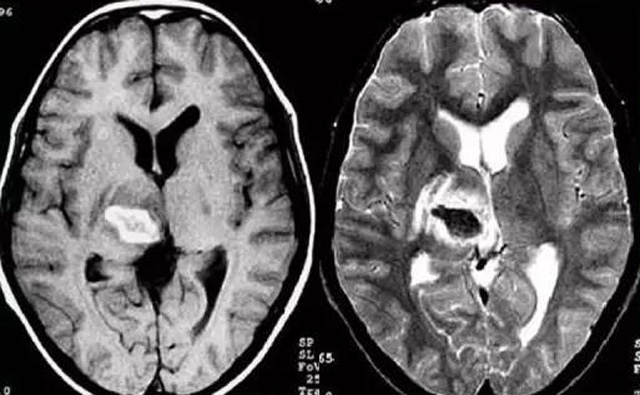

經(jīng)顱多普勒超聲(TCD)磁共振MRI檢查腦出血診斷的作用是什么?

發(fā)現(xiàn)病人出血腦梗相關(guān)癥狀時候第一時間就醫(yī),需要攜帶以往的影像檢查資料。向醫(yī)生提供相關(guān)的病史基本資料。做影像檢查時候需要全身不攜帶金屬物品。檢查時候身體保持不動,不然偽影對檢查結(jié)果有干擾。磁共振MRI發(fā)現(xiàn)缺血性卒中后,幫助進一步查找病因。由于CT上小腦跟腦干顱骨影響,容易導(dǎo)致漏診。MRI檢查可以對CT檢查不足的補充。短暫的腦缺血TIA也需要進行影像檢查。短暫性缺血一般10幾分鐘后好轉(zhuǎn)。檢查目的可以確定TIA的病因。降低腦梗死的發(fā)生率。磁共振有助于排出TIA表現(xiàn)的顱內(nèi)病變,有診斷及時治療的價值。磁共振MRI檢查時間比較長,不太適合急診病人。但是可以發(fā)現(xiàn)腦干小腦的出血問題。因為急性腦梗死的早期和急性期,缺血區(qū)的腦組織還沒有完全壞死,頭顱CT不能顯示病灶,所以就需要MRI磁共振檢查,這個對陳舊跟亞急性出血顯示比較好。缺點性價比不高,費用比較貴。頭顱的磁共振MRI在發(fā)病后的幾天CT的敏感降低時候發(fā)揮大作用。,MRI可作為診斷蛛網(wǎng)膜下腔出血和了解破裂動脈瘤部位的一種重要方法,必要時進一步進行DSA檢查,幫助制訂臨床的手術(shù)治療方案,

經(jīng)顱多普勒超聲(TCD)有效沒有創(chuàng)傷性的檢查方法,是檢查腦血管的設(shè)備之一,它目前廣泛應(yīng)用于臨床,檢查判斷腦出血卒中的頭顱里面的內(nèi)動脈外動脈的病變問題。診斷顱內(nèi)動脈狹窄或閉塞性病變。顱外頸部動脈狹窄或閉塞性病變,評價顱外動脈嚴(yán)重狹窄或閉塞對顱內(nèi)血流速度的影響。頸動脈內(nèi)膜剝脫手術(shù)前預(yù)測夾閉作用、術(shù)后評估顱內(nèi)血流變化。